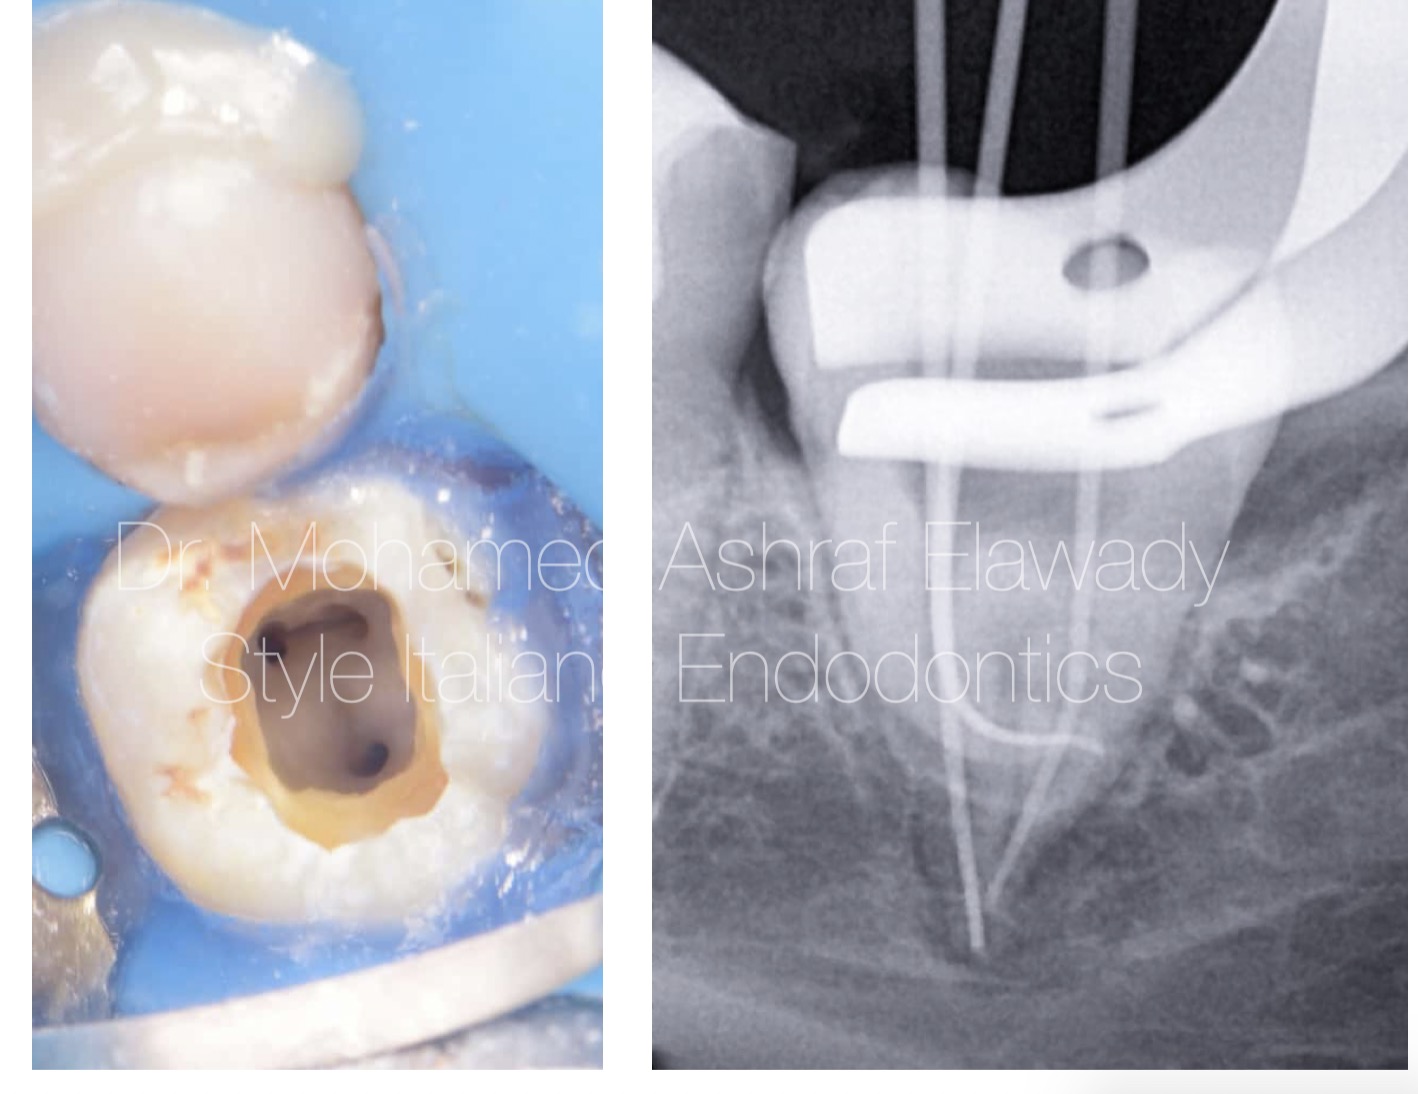

Starting with isolation prevents contamination, enhances visibility, and ensures a dry, clean environment for effective root canal treatment.

Fig. 3

Glide path creation in severely curved canals ensures smooth instrument navigation, reduces the risk of ledging, and facilitates safe shaping.

Fig. 4